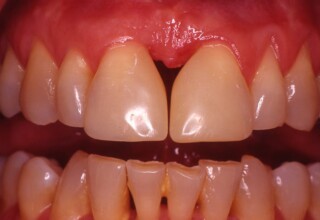

Λεύκανση απονευρωμένου κεντρικού τομέα και αύξηση ύψους με ρητίνη

Τα απονευρωμένα δόντια πολλές φορές χάνουν την φωτεινότητα τους και σκουραίνουν σε αντιαισθητικό επίπεδο. Η λεύκανση τους προϋποθέτει άψογη απονεύρωση και υπομονή. Τοποθετείται ένα σφράγισμα στη ρίζα του δοντιού για να περιοριστεί η δράση του λευκαντικού υγρού μόνο στο τμήμα του δοντιού που είναι εμφανές στην στοματική κοιλότητα. Στην συνεχεία απαιτούνται 1-5 σύντομες συνεδρίες τοποθέτησης του λευκαντικού υλικού. Μετά τον αποχρωματισμό του δοντιού τοποθετείται ένα σφράγισμα ρητίνης με άψογη συγκόλληση για όσο το δυνατόν μακροχρόνια αποφυγή της μικροδιείσδυσης.